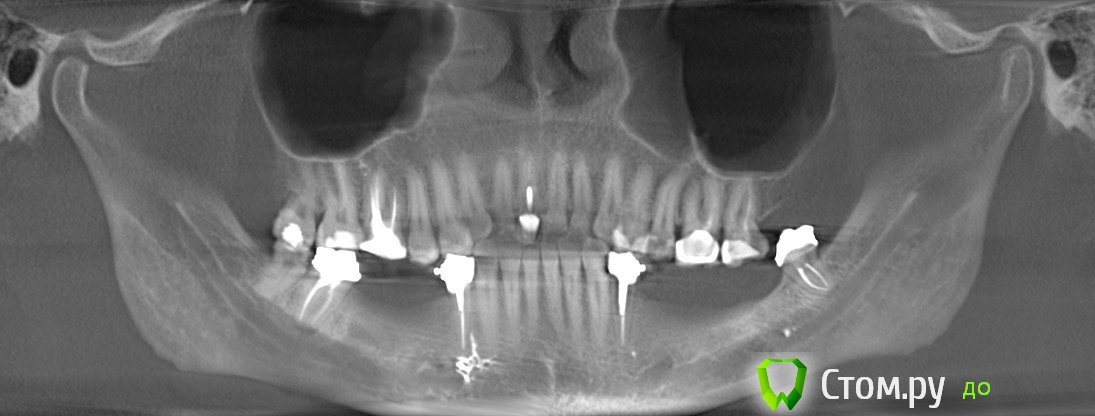

kriokov Опубликовано 23 ноября, 2014 Поделиться Опубликовано 23 ноября, 2014 похоже на перелом я бы не стал с выводами торопиться,К ТопикстартеруЕсли не затруднит, сделайте из кт панораму (оптг, это возможно сделать почти в любой программе просмотрщике , которая есть на диске), одну до забора блока, вторую после установки блока , и залейте обе. Мне кажется обычные панорамные снимки будут более информативны, особенно в ситуации после забора и трансплантации блока. имхо 2 Ссылка на комментарий

Марьяна Опубликовано 23 ноября, 2014 Автор Поделиться Опубликовано 23 ноября, 2014 (изменено) я бы не стал с выводами торопиться,К ТопикстартеруЕсли не затруднит, сделайте из кт панораму (оптг, это возможно сделать почти в любой программе просмотрщике , которая есть на диске), одну до забора блока, вторую после установки блока , и залейте обе. Мне кажется обычные панорамные снимки будут более информативны, особенно в ситуации после забора и трансплантации блока. имхо Хорошо, вот:Позже закину ссылку на дайкомы. Изменено 23 ноября, 2014 пользователем Марьяна Ссылка на комментарий